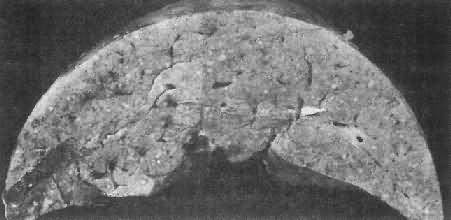

随着病变的发展形成假结核结节,最后发生纤维化,虫卵也逐渐死亡及钙化。由于虫卵的反复沉着,引起肠粘膜反复发生溃疡和肠壁纤维化,最终导致肠壁增厚变硬,甚至肠腔狭窄和肠梗阻。肠粘膜粗糙不平,萎缩,皱襞消失,除见小溃疡外,还可见多发性小息肉(图19-8)。由于肠壁结缔组织增生,使以后到达肠壁的虫卵难于排入肠腔,故晚期患者粪便中不易查见虫卵,一般需做直肠粘膜压片、活检或皮内试验等来确诊本病。

图19-8 慢性血吸虫病的结肠

肠壁增厚,粘膜粗糙不平,多处粘膜呈息肉样增生